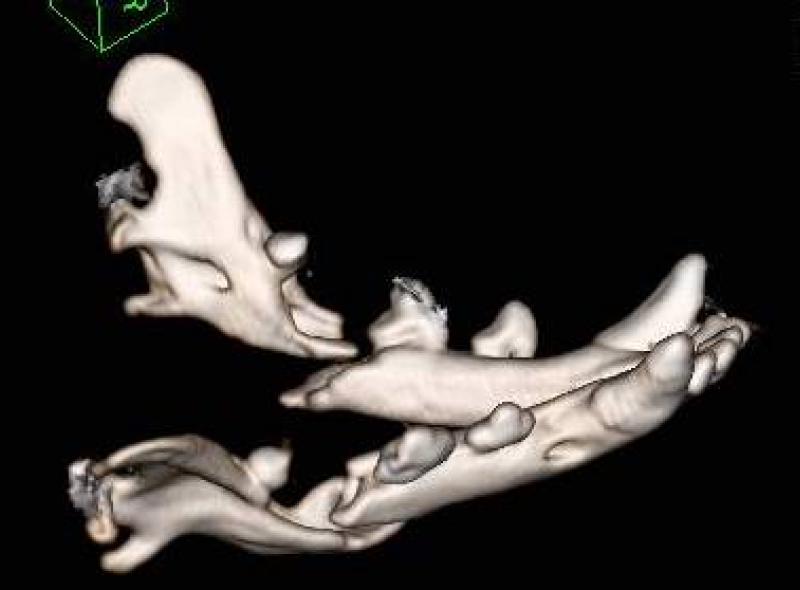

顎骨折(歯周病による下顎骨折)

歯周病や交通事故、衝突などにより、顎の骨を骨折してしまうことがあります。

特に、小型犬種では、顎と歯の大きさが相対的に近くなるため、歯周病が進行した時、下顎骨が吸収(溶けて)骨折することがあります。

治療は、歯周病の治療を行い、病因となっている歯は抜歯し、固定に使えそうな歯または支持組織が残っている場合にはそれを利用して固定を行います。

骨折は、骨折端を合わせて固定することで、約1ヶ月で癒合してきます。

ただし、口は常に動かして使う組織ですので、“固定”が難しく、その治癒が難しいことがあります。